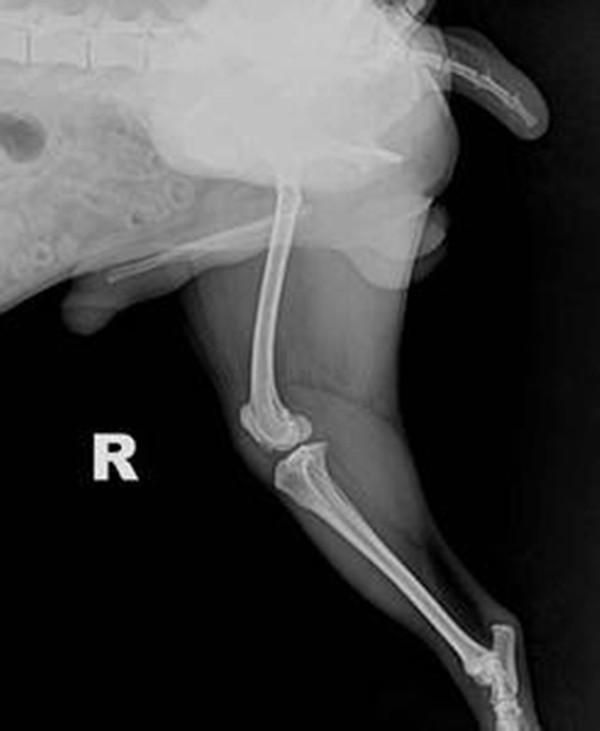

当患犬出现破行时,通过手触诊整个患肢无痛觉应重点怀疑本病,对出现明显破行者,用手检查髌骨可见明显脱位现象。有条件的动物医院应通过X光诊断,在X光正位片可见髌骨位于股骨的内侧或外侧,而不在股骨滑车中,同时可见滑车沟变浅、胫骨近端弯曲转位和股胫关节成角异常。当幼犬的髌骨钙化不全时,其移位则很难显示。在X光侧位片上,可见髌骨不在滑车沟内而是与股骨髁重叠。